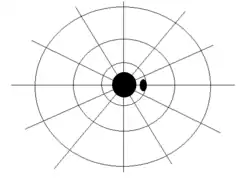

- Optic neuritis involving external fibers of the optic nerve causes tunnel vision.[4]

- Optic neuritis involving internal fibers of the optic nerve causes central scotoma.[4] lf unilateral central scotoma is detected, careful observation of the temporal visual field of other eye is essential to rule out the possibility of compressive lesions at the junction of optic nerve and optic chiasm.[5]